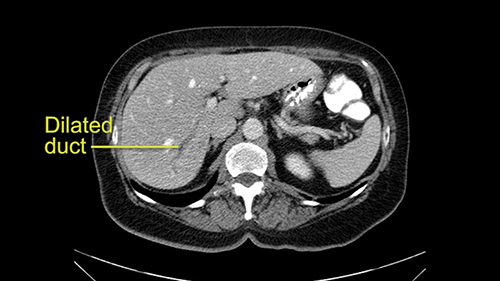

The third issue for this patient is that in Segment 7, I notice that there is intrahepatic ductal dilatation due to a small tumor causing obstruction. Now this tumor is not well-visualized on the most recent CT scan but I want to carefully evaluate the bile duct, where the obstruction is, so at the time of surgery I can be sure to remove the affected bile duct as well as the small tumor that is causing the ductal dilatation.

So in light of the CT findings, the plan for this patient is a right hemihepatectomy that would encompass all the small tumors including the one in 4a-8, 5, 6-7; and the reason that I would do a full right hemihepatectomy is because of the intraductal dilatation in Segment 7 that makes me suspicious that there is a tumor that cannot be removed with simple wedge resections.

My name is Steven Gallinger, I’m a professor of surgery at the University of Toronto and an HPB surgeon at the University Health Network. I’ve been asked to comment on this case and discuss preoperative planning, potential slowing down moments. It’s an interesting 65-year old woman with right sided colon cancer and synchronous liver metastases: small metastases in the right lobe of the liver and she had the primary tumor resected and then underwent neoadjuvant chemotherapy for her small liver metastases in Segments 4, 5, 6 and 7. The distribution of the metastases is interesting. They are small lesions, but the interesting additional feature is isolated segmental dilatation of the Segment 7 bile duct which suggests an intrabiliary metastasis somewhere near the origin of the main Segment 7 duct. Because I can trace it close to the porta [hepatis], I would assume that it’s pretty close to the bifurcation of the main right sided bile ducts but I can’t actually see the actual tumor. It’s really just presumptive.

She underwent neo-adjuvant chemotherapy and then had a series of additional investigations and the one that I’m focusing on in more finer detail is an MRI with Primovist and I’ve had the benefit of looking at the report. The main issues are in Segments 5,6, and 7. Three small metastases that remain and the radiologist also comments on the lack of biliary dilatation which was present before; implying that the intrabiliary metastasis somewhere at the origin of the Segment 7 duct, has regressed or been adequately well treated with chemotherapy. That’s probably where the difficult decision making comes in the OR. So from an oncologic point of view, I would plan for a right hepatic lobectomy. The rationale would be that this would include the more peripheral Segment 5, 6, 7 metastases that are obvious but also would take care of the presumed Segment 7 intrabiliary metastasis that does not actually visualize on any of the scans but is assumed to be there with evidence of the duct dilatation which then resolved. One could argue whether we should preserve liver and ignore that duct dilatation that was there before but I think my own preference would be to resect the right lobe and that would certainly include any residual disease in that Segment 7 bile duct and moreover, coming back to do a completion right hepatic lobectomy would be difficult particularly around the porta where this metastasis is presumably still there and even if its quite small.

I am Professor Jacques Belghiti, hepatobiliary surgeon. I practiced at Beaujon Hospital at Paris Diderot University Paris 7. I will discuss the case of a 65-year old patient who has hepatic metastases from a colon cancer operated on one year before. Two particular points with this patient: She has had a cholecystectomy at the time of colectomy, and at the discovery of the lesions in which there were 3, all located in the right liver, we noted the existence of biliary dilatation. This biliary tract dilatation could have been a consequence of the cholecystectomy, or due to a particular form of metastasis with biliary infiltration; and my impression is that the second hypothesis should be supported for two reasons. The first reason is that on the initial CT scan, we had a feeling that the biliary tract dilatation was associated with a small tumor/lesion. The second reason is that the dilatation decreased after several courses of chemotherapy. I don’t know how many courses of chemotherapy she had, but in any case, there exists some lesions of the hepatic parenchyma, with steatosis that may have been a consequence of this chemotherapy. After several courses of chemotherapy, we see at least 2 lesions persisting in the posterior sector of the right liver and dilatation of the biliary tracts. There might be another lesion at the junction of Sg 5 and 8. So this patient should now be operated on since we are faced with lesions that persisted after chemotherapy.

Coming up a little bit higher. There’s a little bit of biliary dilatation as well. On the right side of the liver. Which may be nothing but it may be an indicator or harbinger of nodal disease in the hepatoduodenal ligament so something to be aware of. If the enzymatic liver function tests are normal and there’s no evidence of a stone in the common bile duct on cross sectional imaging you wouldn’t need to do anything about it but just to be aware of that.![[RHV]](jpg/preop_as_p4.jpg)

In this case, with this specific case, one of the things that I was a little concerned about was that biliary dilatation because biliary dilatation isn’t normally part of the kind of landscape of metastatic colorectal cancer unless there are lymph nodes enlarged in the hepatoduodenal ligament. So I would, in this case, I would specifically look at the hepatoduodenal ligament to see whether she’s got enlarged lymph nodes. If they’re enlarged and they spread all the way down, if there’s a chain of enlarged lymph nodes running behind the back of pancreas, that can be seen as contraindication to liver resection because it means that there’s regional metastatic disease which isn’t going to be resected by a liver resection. So that biliary dilatation is a little bit of a source for concern. The other thing is that there is a way of predicting how patients will do from liver resection. Quite often referred to as the Fong Score. Here, there are more than one metastases, 3 or 4 metastases. So that’s the one point that’s beginning to indicate that maybe the prognosis is a little worrying but it wouldn’t stop you doing a resection. A resection would be an appropriate thing to do here.